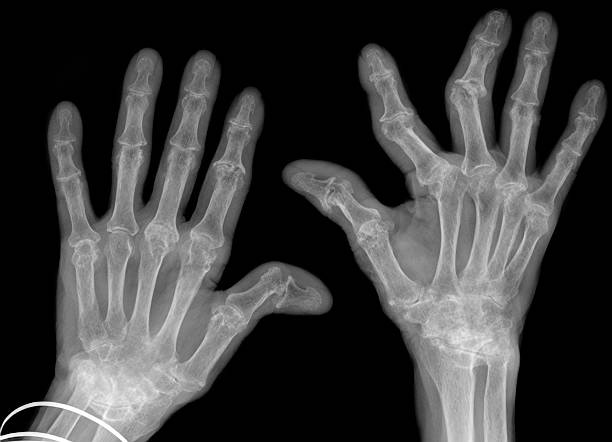

✔ ③ 영상 검사

- X-ray

- 초음파

- MRI (초기 진단 시 활용)

초기에는 X-ray에서 이상이 없을 수도 있어

초음파나 MRI가 조기 진단에 도움이 된다.

- 단순 퇴행성 관절염과 다름

- 양쪽 관절에 대칭적으로 발생

- 시간이 지날수록 관절 변형 가능